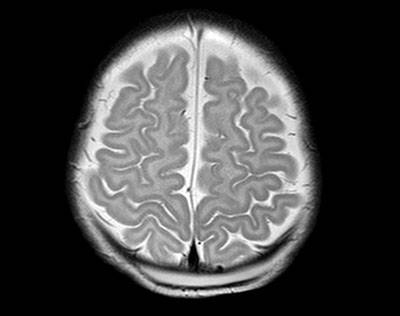

TAC y RMN cerebral: colección líquida subgaleal parietal medial que cruza suturas con igual señal al LCR en las diferentes secuencias. Mide aproximadamente 64mm x 30mm x 5mm. La colección es atravesada por un pequeño trayecto vascular venoso que corresponde con una vena emisaria que se extiende desde espacio subaracnoideo, atraviesa la calota y llega a vena superficial cerebral (trayecto vascular normal a ese nivel), pero no hay contenido hemorrágico en su interior. No se observan defectos óseos patológicos o fracturas de la calota craneal ni en el seno venoso (fotos 2 y 3).